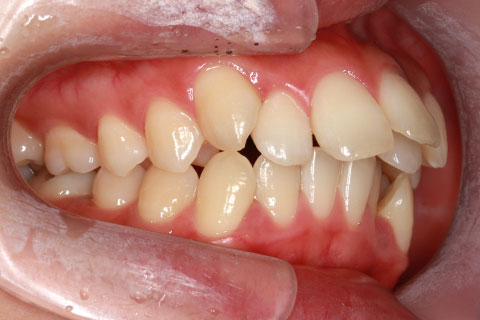

ハーフリンガル矯正4:上の歯のみ舌側矯正で治療(矯正期間24ヶ月)

- 年齢・性別

- 23歳女性

- 治療期間

- 2年0ヶ月

- 抜歯

- 上下4番抜歯

- 治療費

- 110万円

- 備考

- マルチブラケットを用いた矯正治療

- 治療内容

- 施術の副作用(リスク)

- 表側矯正と比較して、前歯のラビッティング(舌側傾斜)を起こしやすい。